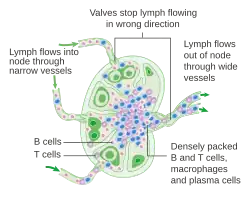

Cells

In the lymphatic system a lymph node is a secondary lymphoid organ.[5] Lymph nodes contain lymphocytes, a type of white blood cell, and are primarily made up of B cells and T cells.[5] B cells are mainly found in the outer cortex where they are clustered together as follicular B cells in lymphoid follicles, and T cells and dendritic cells are mainly found in the paracortex.[19]

There are fewer cells in the medulla than the cortex.[5] The medulla contains plasma cells, as well as macrophages which are present within the medullary sinuses.[19] In case of diseases like cancer, macrophages within the lymph nodes may play pro-cancerous role by deleting anticancer T cells e.g., PD-L1+ macrophages in lymph nodes, facilitated by anticancer vaccines, can directly delete CD8+ T cells via extrinsinc apoptotic signalling.[20]

As part of the reticular network, there are follicular dendritic cells in the B cell follicle and fibroblastic reticular cells in the T cell cortex. The reticular network provides structural support and a surface for adhesion of the dendritic cells, macrophages and lymphocytes. It also allows exchange of material with blood through the high endothelial venules and provides the growth and regulatory factors necessary for activation and maturation of immune cells.[21]

Lymph flow

Lymph enters the convex side of a lymph node through multiple afferent lymphatic vessels, which form a network of lymphatic vessels (Latin: plexus) and flows into a space (Latin: sinus) underneath the capsule called the subcapsular sinus.[5][4] From here, lymph flows into sinuses within the cortex.[4] After passing through the cortex, lymph then collects in medullary sinuses.[4] All of these sinuses drain into the efferent lymphatic vessels to exit the node at the hilum on the concave side.[4]

These are channels within the node lined by endothelial cells along with fibroblastic reticular cells, allowing for the smooth flow of lymph. The endothelium of the subcapsular sinus is continuous with that of the afferent lymph vessel and also with that of the similar sinuses flanking the trabeculae and within the cortex. These vessels are smaller and do not allow the passage of macrophages so that they remain contained to function within a lymph node. In the course of the lymph, lymphocytes may be activated as part of the adaptive immune response.

There is usually only one efferent vessel though sometimes there may be two, in contrast to the multiple afferent channels that bring lymph into the node.[22] Medullary sinuses contain histiocytes (immobile macrophages) and reticular cells, the former of which, along with T and B cells, become activated in the presence of antigens through lymphatic flow. The fewer efferent vessels allow this flow to be slowed, providing time to activate and distribute a larger number of immune cells in the event of an infection.